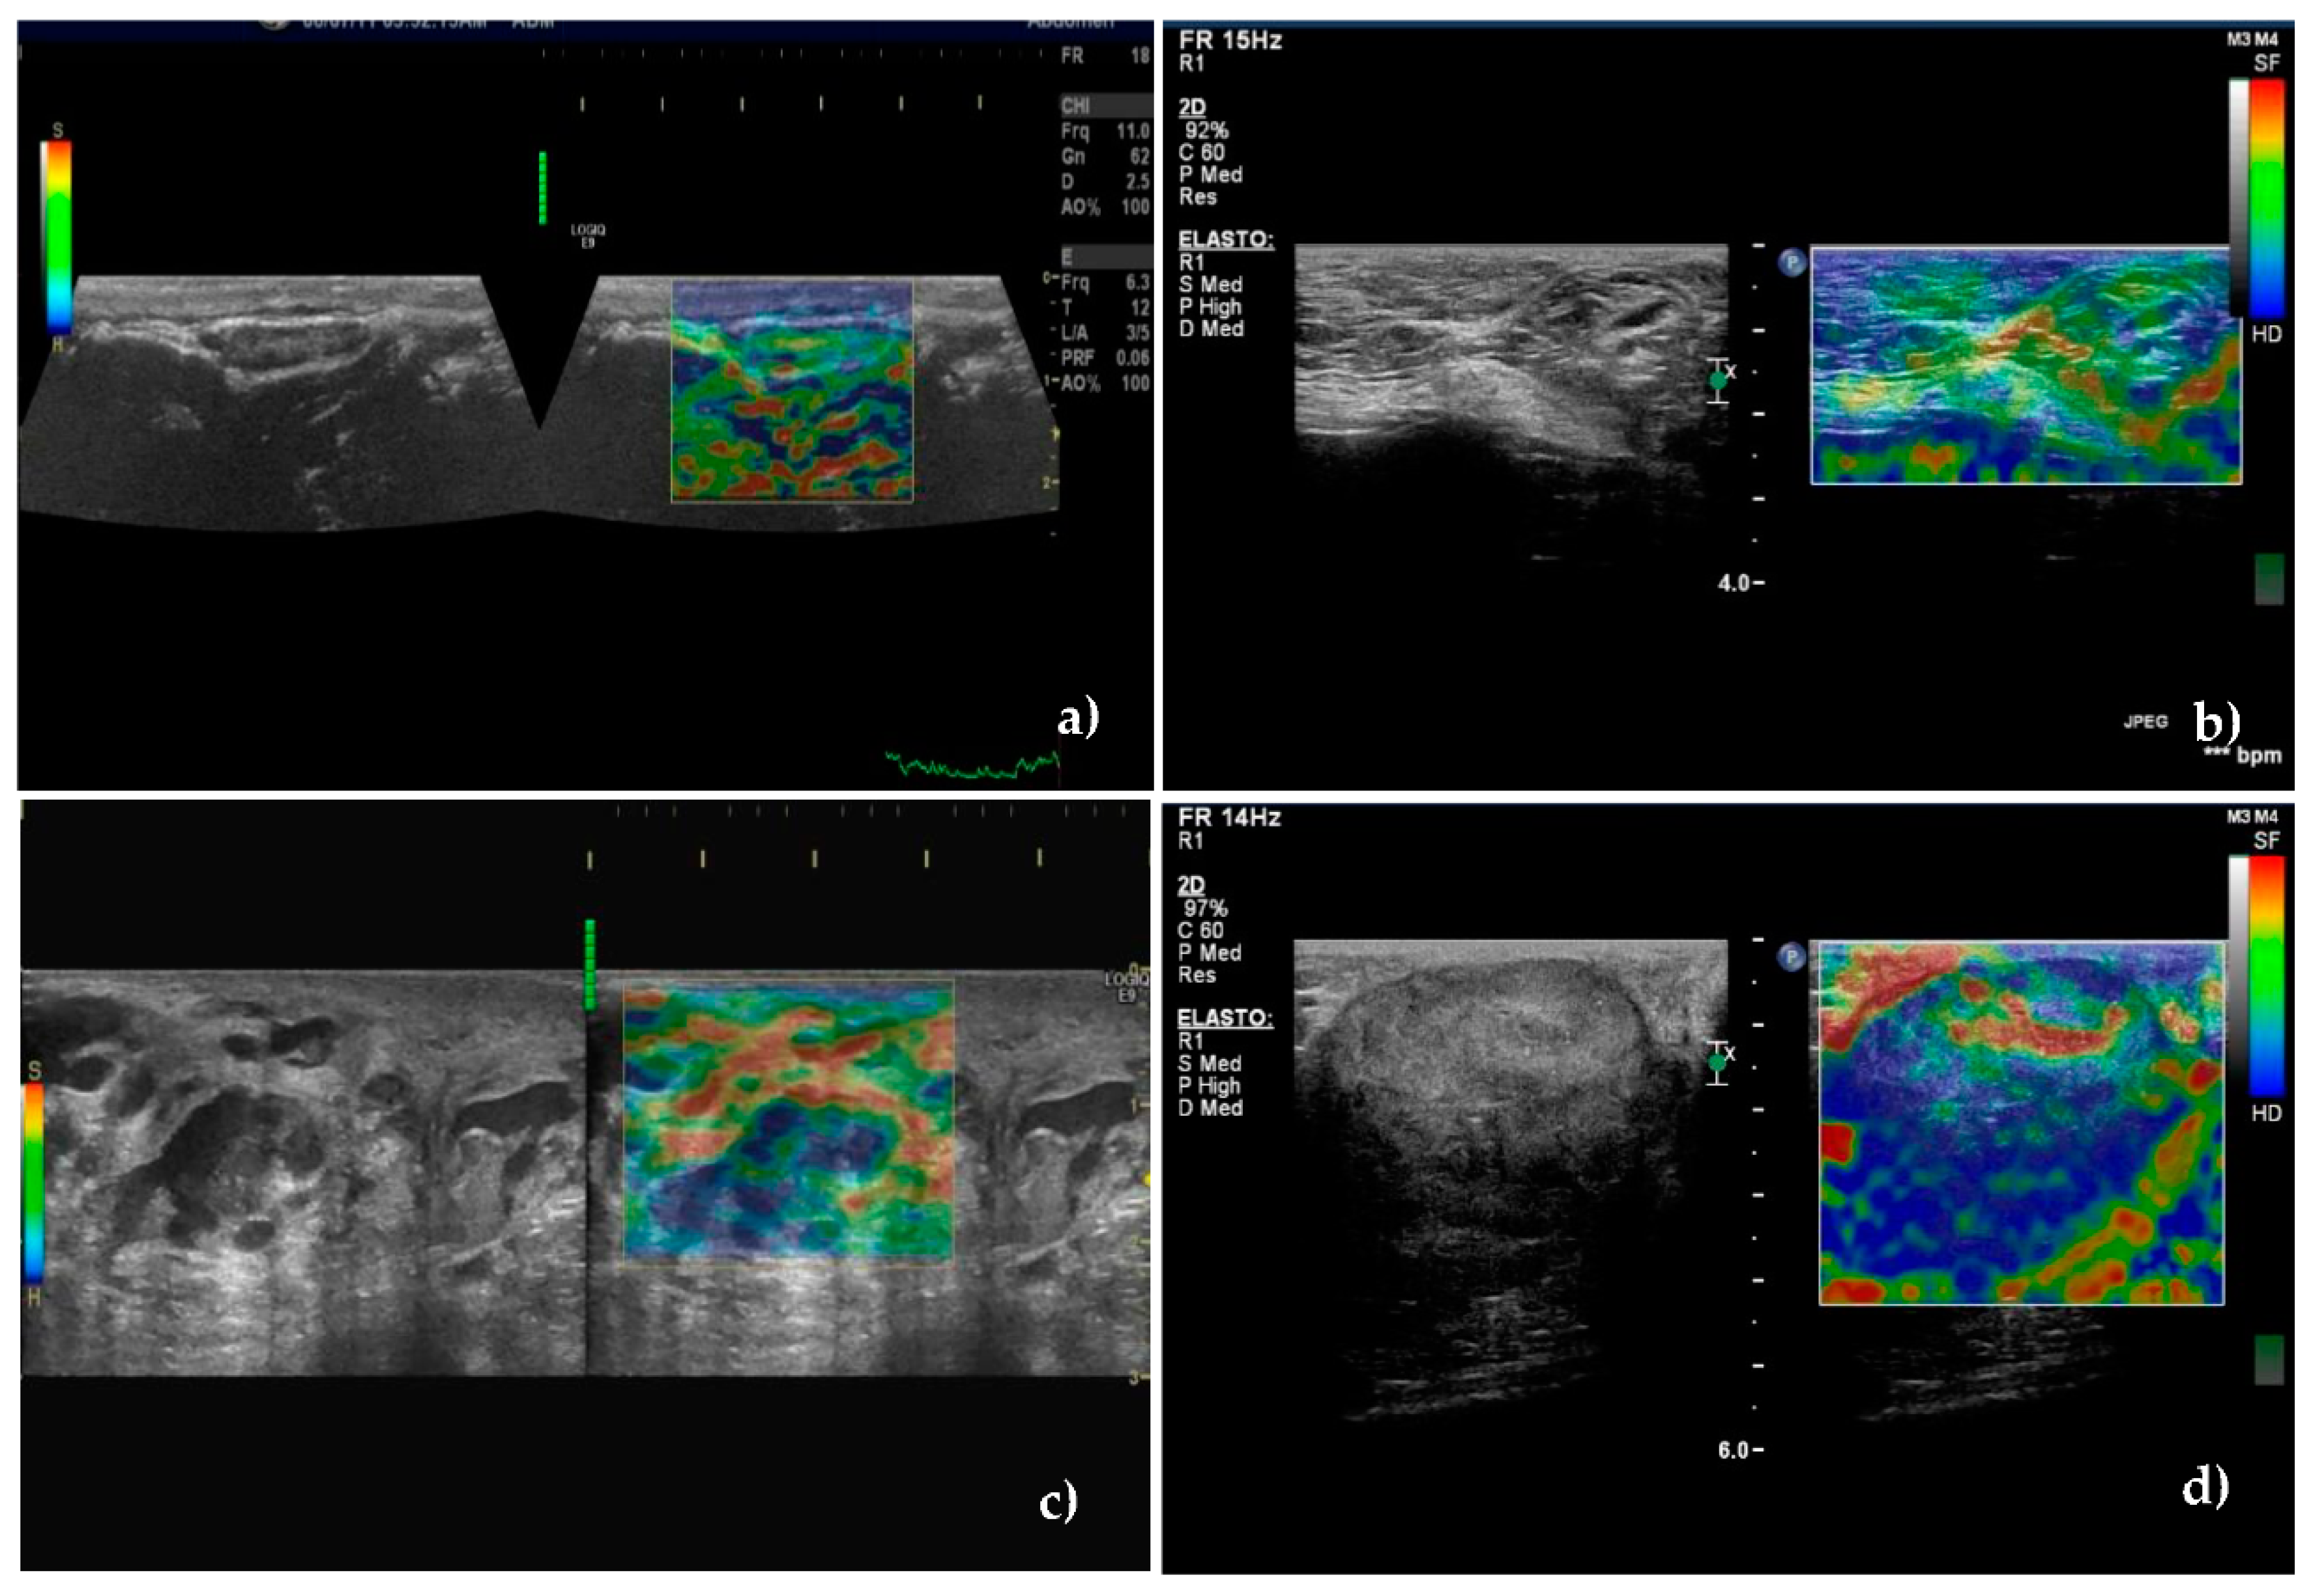

3.4. Real-Time Elastography

| REAL-TIME ELASTOGRAPHY—LYMPH NODE STIFFNESS ASSESSED BY ELASTICITY STIFFNESS SCORES | |||

| Soft (scores 1 and 2) | 38(90.47) | 6(11.11) | <0.001 |

| Hard (scores 3, 4 and 5) | 6(14.28) | 48(88.88) | |

| Lymph Nodes | 1 | 2 | 3 | 4 | 5 |

|---|---|---|---|---|---|

| Unaffected (N = 42) | 25 (59.5) | 13 (31.0) | 3 (7.1) | - | 1 (2.4) |

| Metastatic (N = 54) | 2 (3.7) | 4 (7.4) | 14 (25.9) | 19 (35.2) | 15 (27.8) |

| p value | <0.001 | ||||